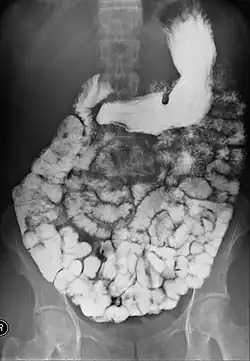

Un transit baryté est un examen radiologique permettant d'étudier le tube digestif haut : œsophage, estomac, duodénum et intestin grêle[1]. Il consiste à faire ingérer par un patient de la baryte, un produit de contraste opaque aux rayons X. Puis des clichés radiographiques sont pris à différents temps, permettant d'explorer l'ensemble du tractus digestif haut à mesure que celui-ci se remplit de baryte.

Cet examen permet de dépister des anomalies telles que tumeurs, polypes, diverticules, inflammation et infection.